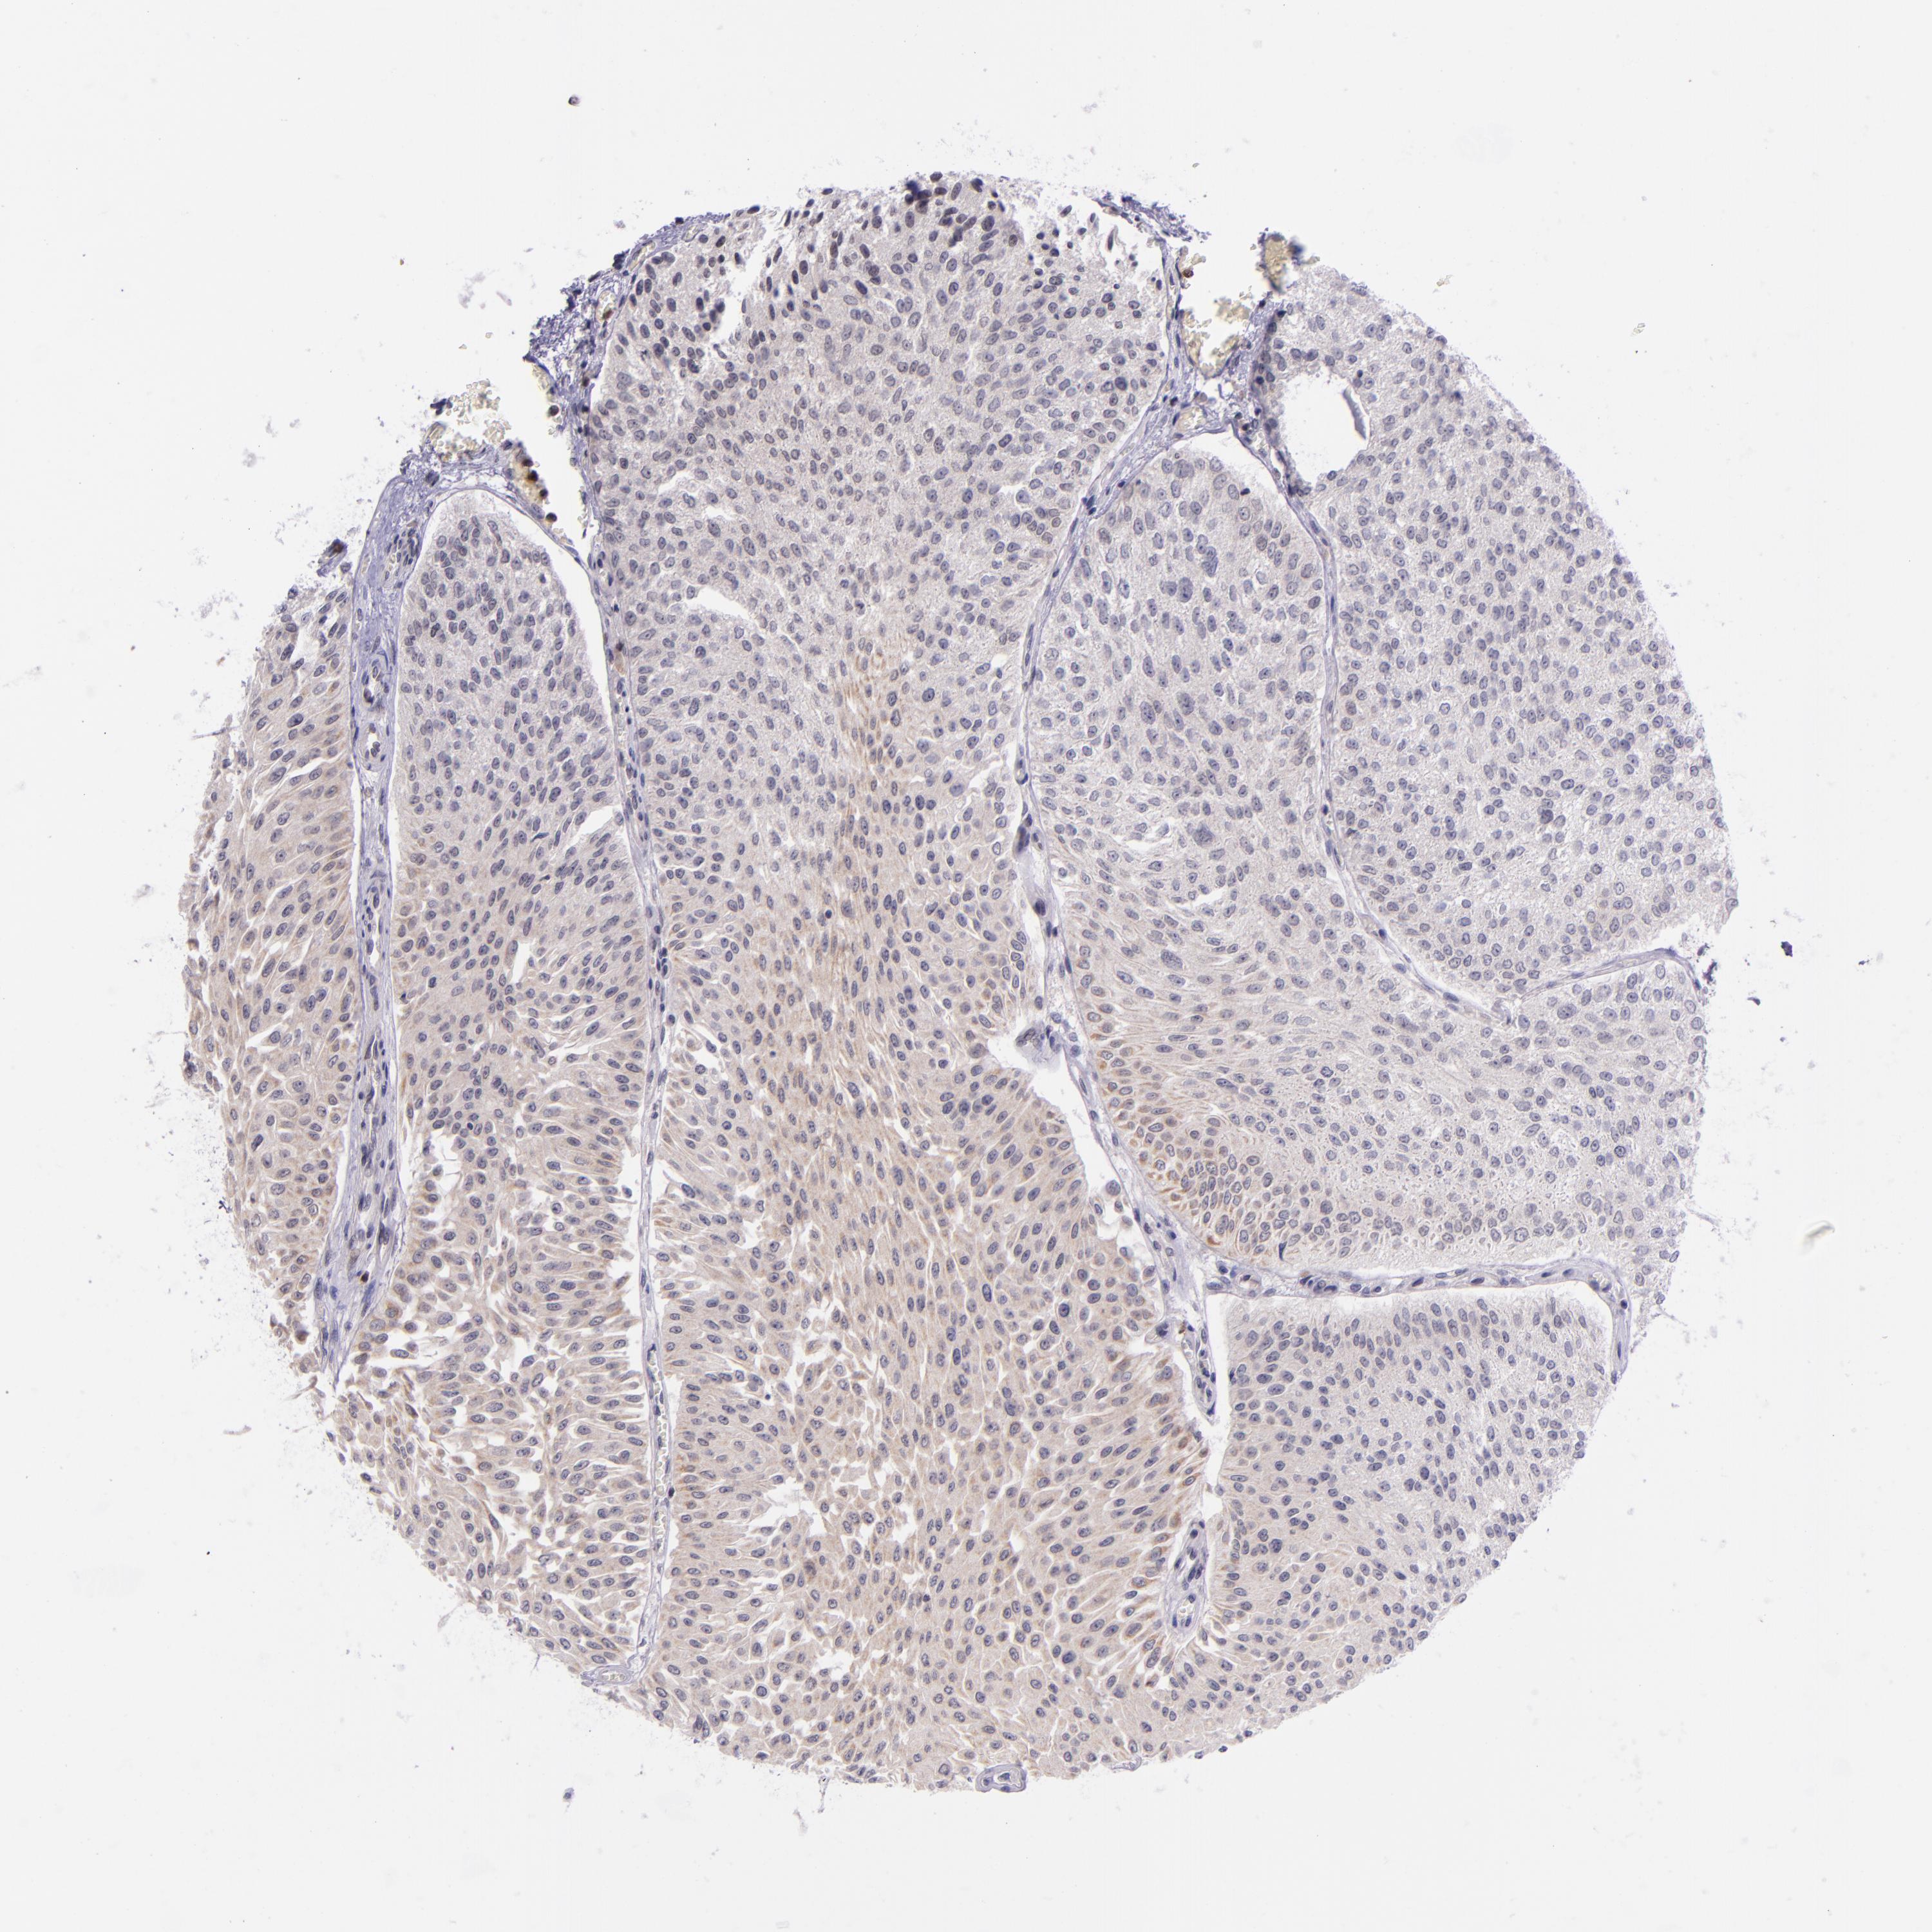

UROTHELIAL CANCER - Protein expressioni

A mouse-over function shows sample information and annotation data. Click on an image to view it in a full screen mode. Samples can be filtered based on level of antibody staining by selecting one or several of the following categories: high, medium, low and not detected. The assay and annotation is described here.

Note that samples used for immunohistochemistry by the Human Protein Atlas do not correspond to samples in the TCGA dataset.

Antibody stainingi

Antibody staining in the annotated cell types in the current human tissue is reported as not detected, low, medium, or high, based on conventional immunohistochemistry profiling in selected tissues. This score is based on the combination of the staining intensity and fraction of stained cells.

Each image is clickable and will lead to virtual microscopy that enables deeper exploration of all samples and also displays staining intensity scores, fraction scores and subcellular localization as well as patient and tissue information for each sample.

Antibody CAB002144

Staining

High

Medium

Low

Not detected

Intensity

Strong

Moderate

Weak

Negative

Quantity

>75%

75%-25%

<25%

None

Location

Nuclear

Cytoplasmic/membranous

Cytoplasmic/membranous,nuclear

Urothelial carcinoma, High grade

Urothelial carcinoma, Low grade